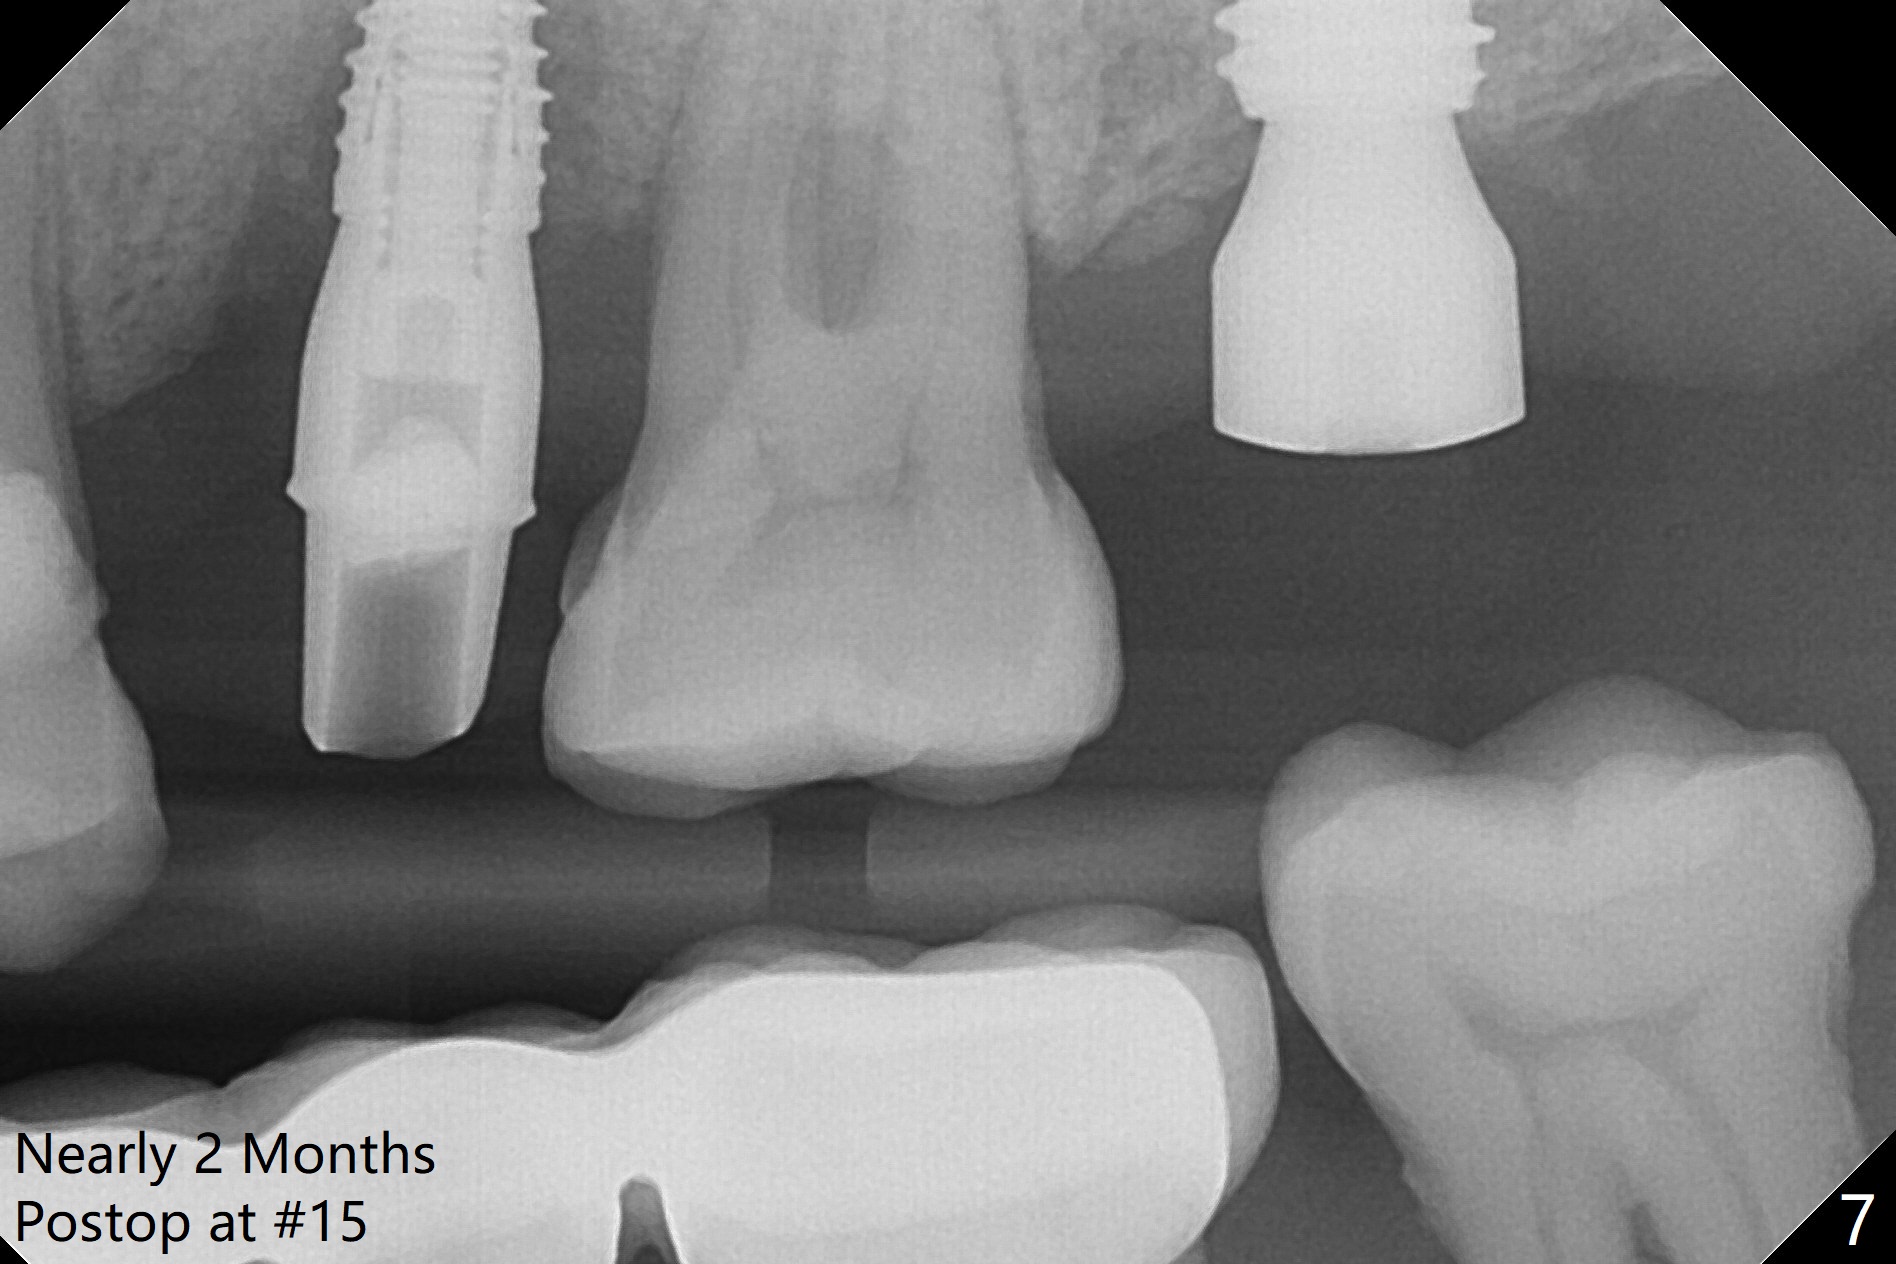

A 1.2 mm initial drill is used to start osteotomy at the site of #15 (Fig.1). After moving the osteotomy distally (with Lindamann bur), the osteotomy is enlarged by DIO Bone Expanders until 2.4/3.7 mm for 18 mm (gingival level) (Fig.2). Following the expander 3.0/4.4 mm, a 5x13 mm UF implant is placed supracrestal (Fig.3,4). After deepening the osteotomy with 3.8 mm drill for 3 mm, the implant is placed deeper by ~ 2 mm (Fig.5 arrow). Since the tooth #18 is supraerupted, a healing abutment (5.5x12(3) mm) is placed (Fig.6: H); the gingiva adapts to the abutment well. Suture is not necessary. The bone remains stable 2 and 4.5 months postop (Fig.7,8). Impression is taken. A crown is delivered nearly 6 months postop (08/07/2017). While there is minimal bone loss at #13 and 15 three years and 4 months post cementation, the tooth #14 and 18 are mobile (Fig.13,14, #13).